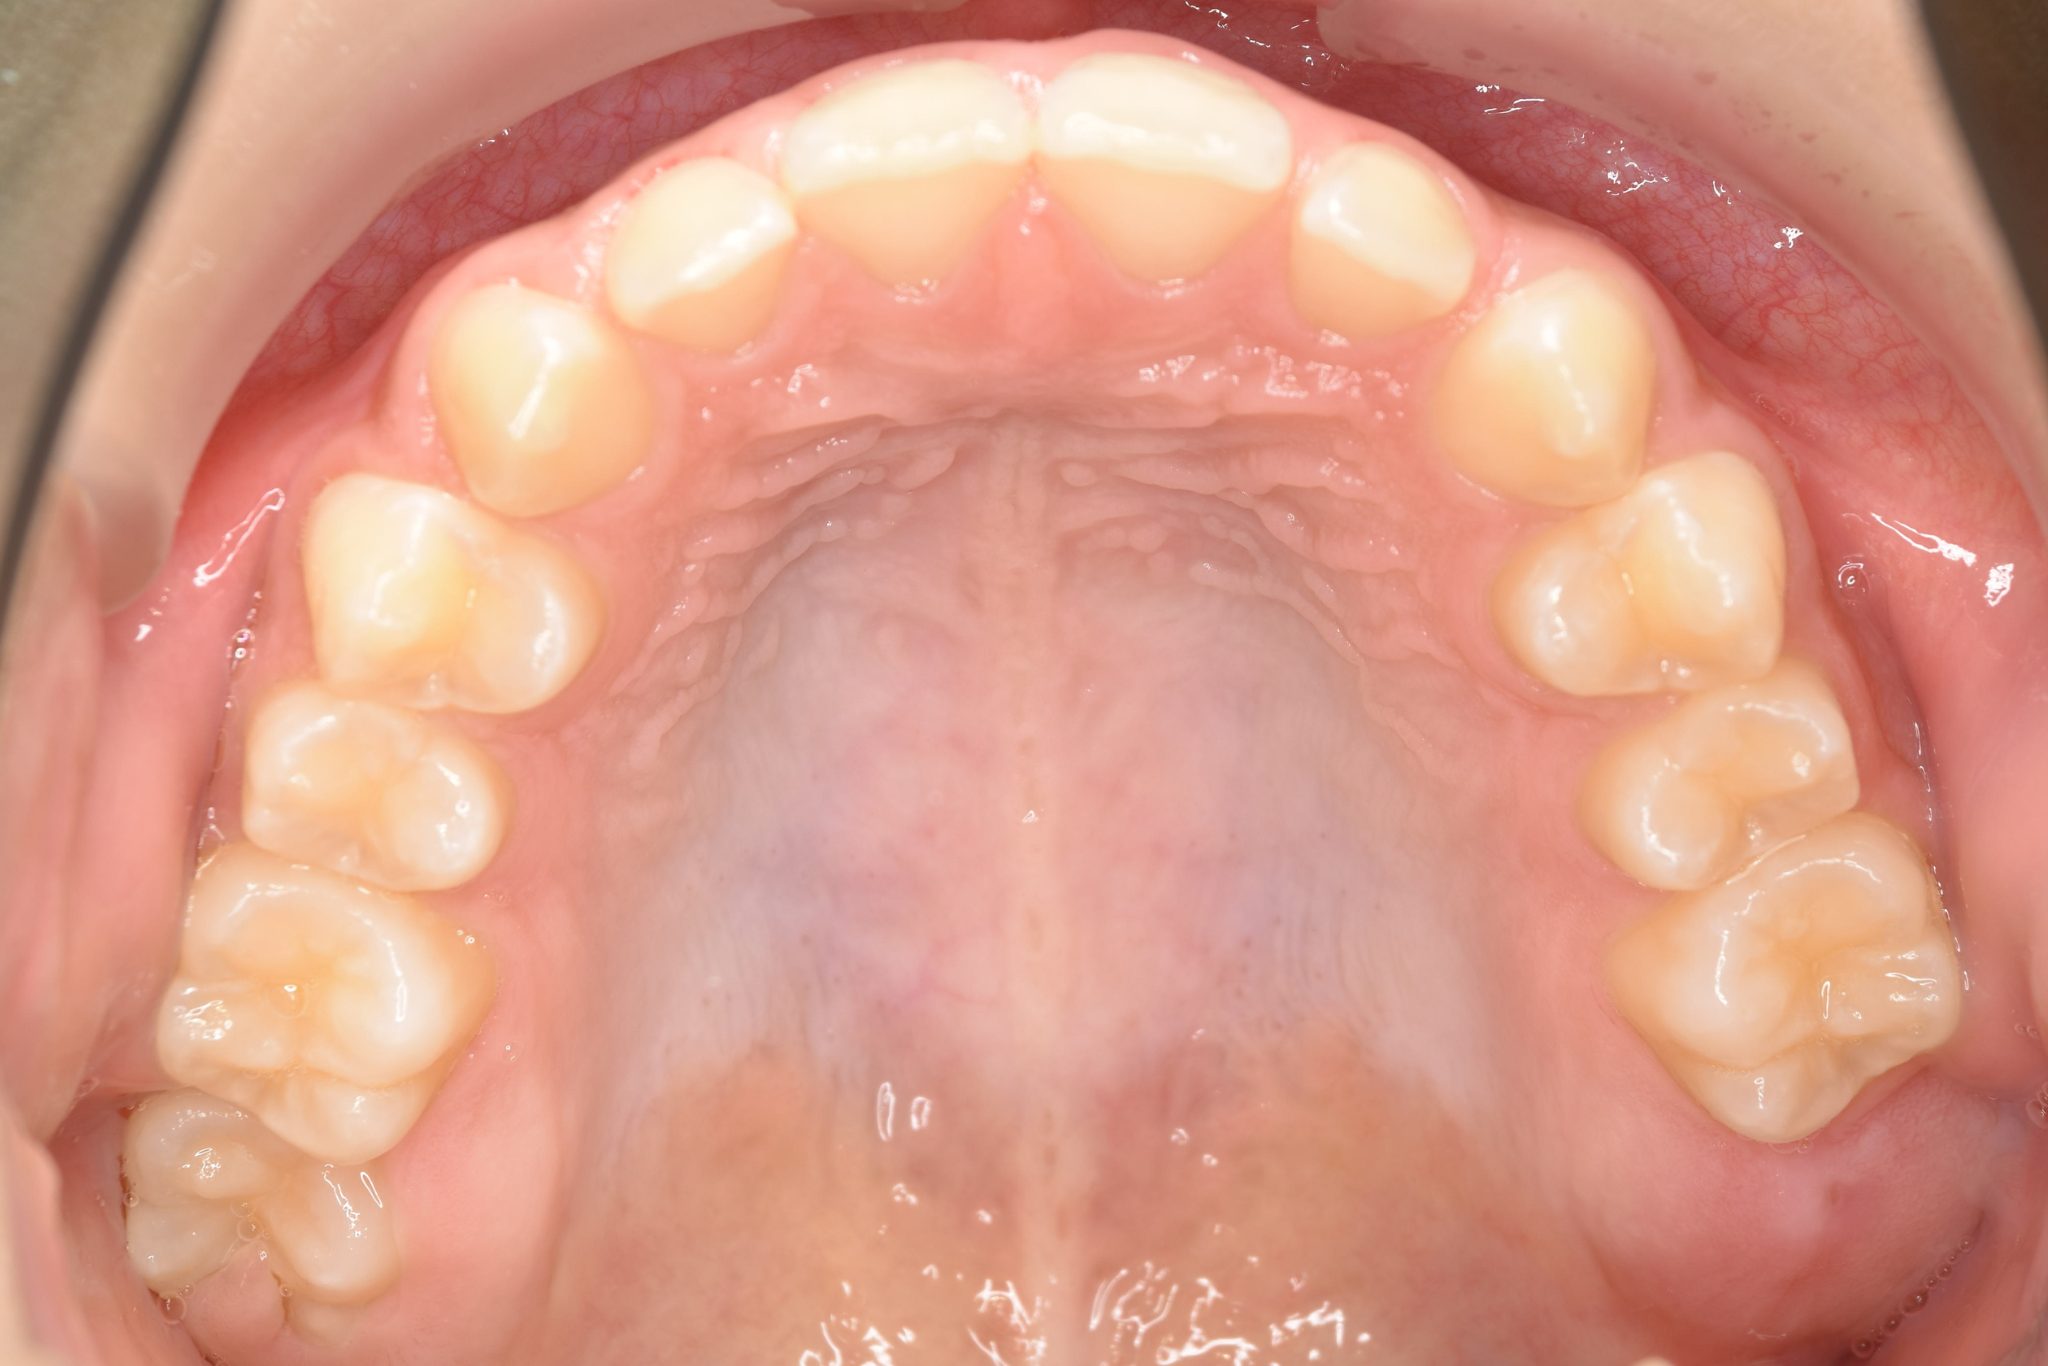

ビフォー

全顎ワイヤー矯正 症例_108

主訴 受け口|前歯がかみ合わない|顔貌

施術内容 小児矯正1期治療

治癒期間 3年11ヶ月間

費用 498,960円(税込)